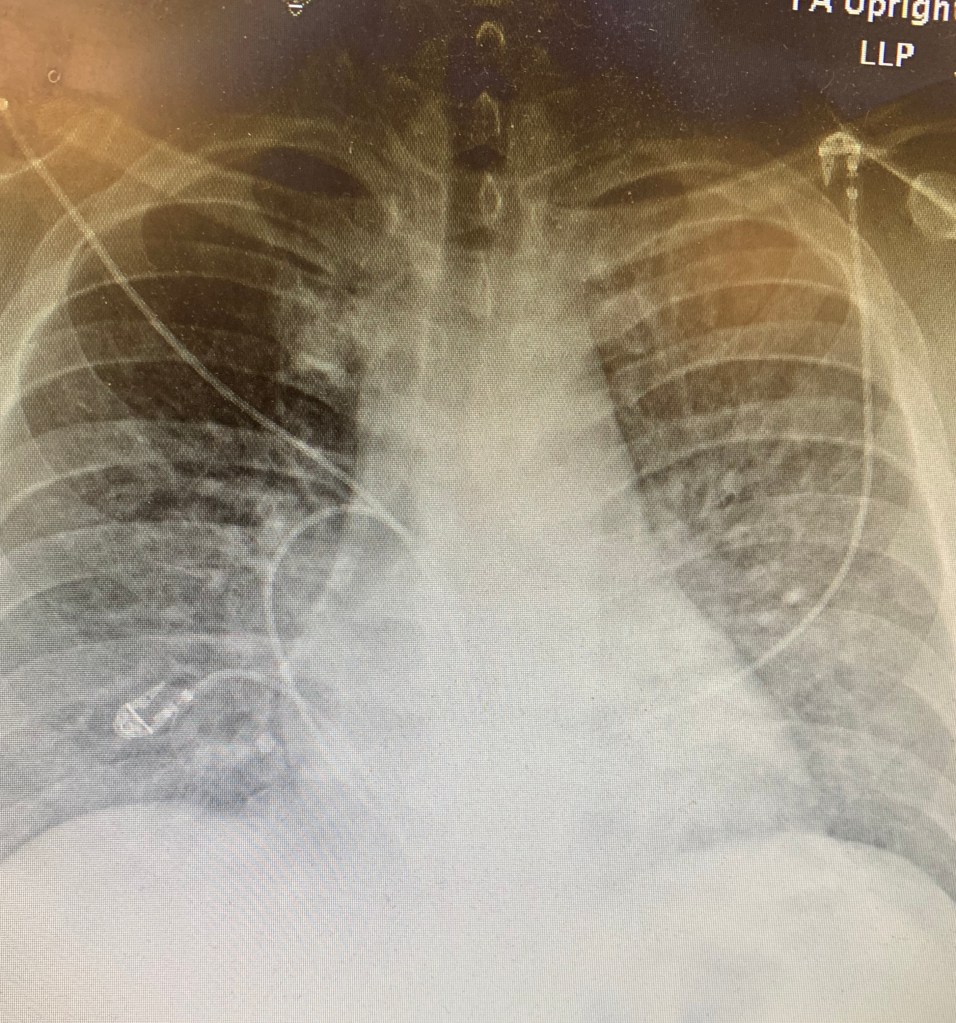

A portable CXR is obtained:

Radiology read: pulmonary edema. The patient has no cardiac history, and so a POC pulmonary and cardiac ultrasound are obtained.

The patient had a CXR concerning for pulmonary edema (but retrospectively it was actually bilateral interstitial opacities or non cardiogenic pulmonary edema consistent with ARDS) with an echo that showed a hyperdynamic heart and a pulmonary ultrasound that showed diffuse b lines in all fields. CT confirmed the diagnosis of diffuse alveolar opacities/pneumonia. The patient did not have heart failure, but rather had sepsis secondary to pneumonia/ARDS.